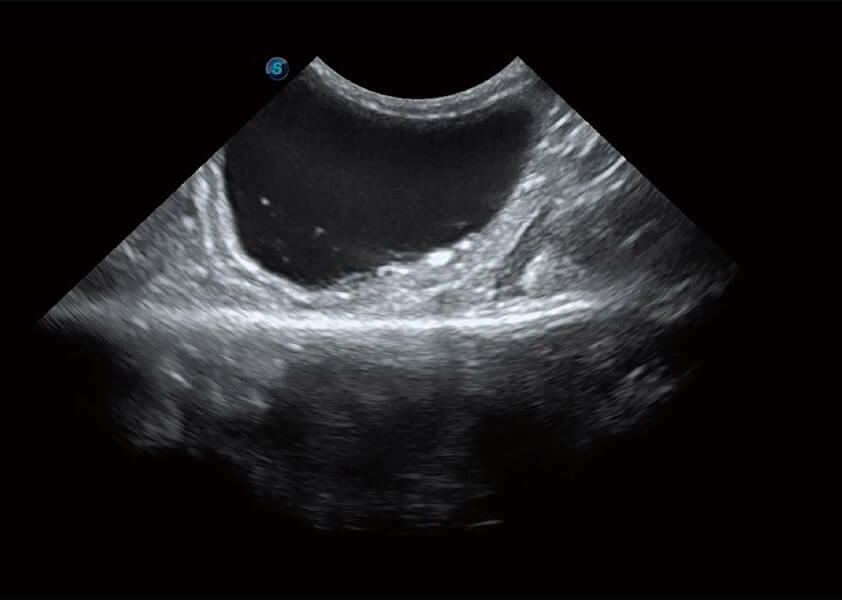

ProPet 60 作為一款高端臺(tái)式動(dòng)物超聲設(shè)備,為動(dòng)物醫(yī)生的日常診斷提供了一系列貼合動(dòng)物臨床需求、解決臨床實(shí)際問題的高級(jí)成像功能。憑借全系列高清探頭,滿足醫(yī)生對(duì)腹部、心臟、生殖、淺表、肌骨等成像的所有需求,切實(shí)幫助您提升檢查效率,提高診斷信心。